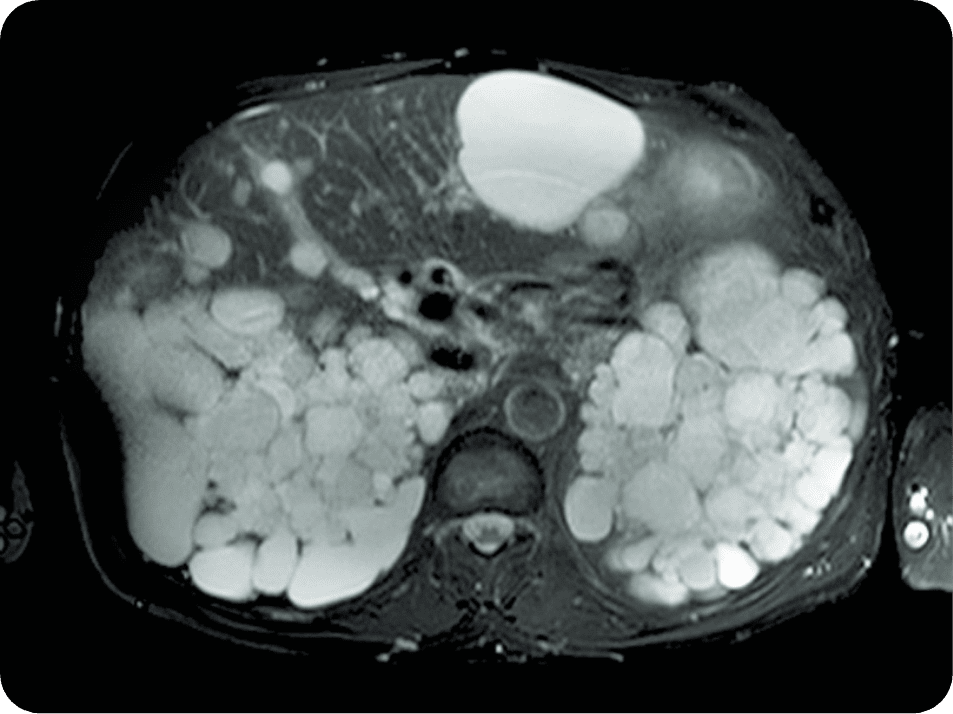

Your nephrologist will request a magnetic resonance imaging

(MRI) or a computed tomography (CT) scan to get a more

detailed picture of your total kidney volume.

An MRI or CT scan reliably measure

kidney size to determine TKV